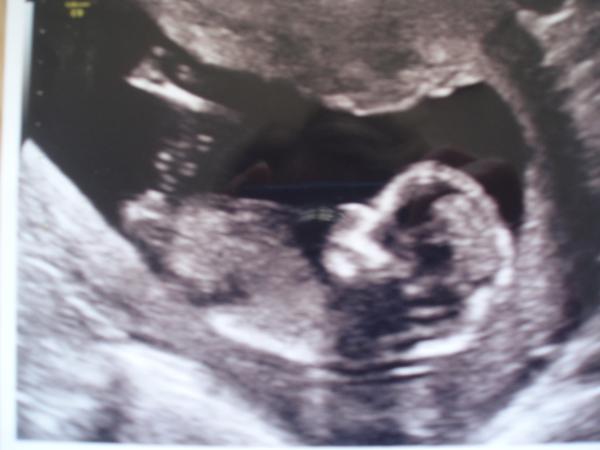

@matysikovad Veliká gratulace!!!!! Krásný brouček. Řekni, řekni, prosím, prosím. 😀

@matysikovad krásný mimoušek 🤐

@matysikovad nádhera 🙂

@matysikovad krásný!!! Jak si tam tak nevinně leží 🙂 Gratuluju 🙂